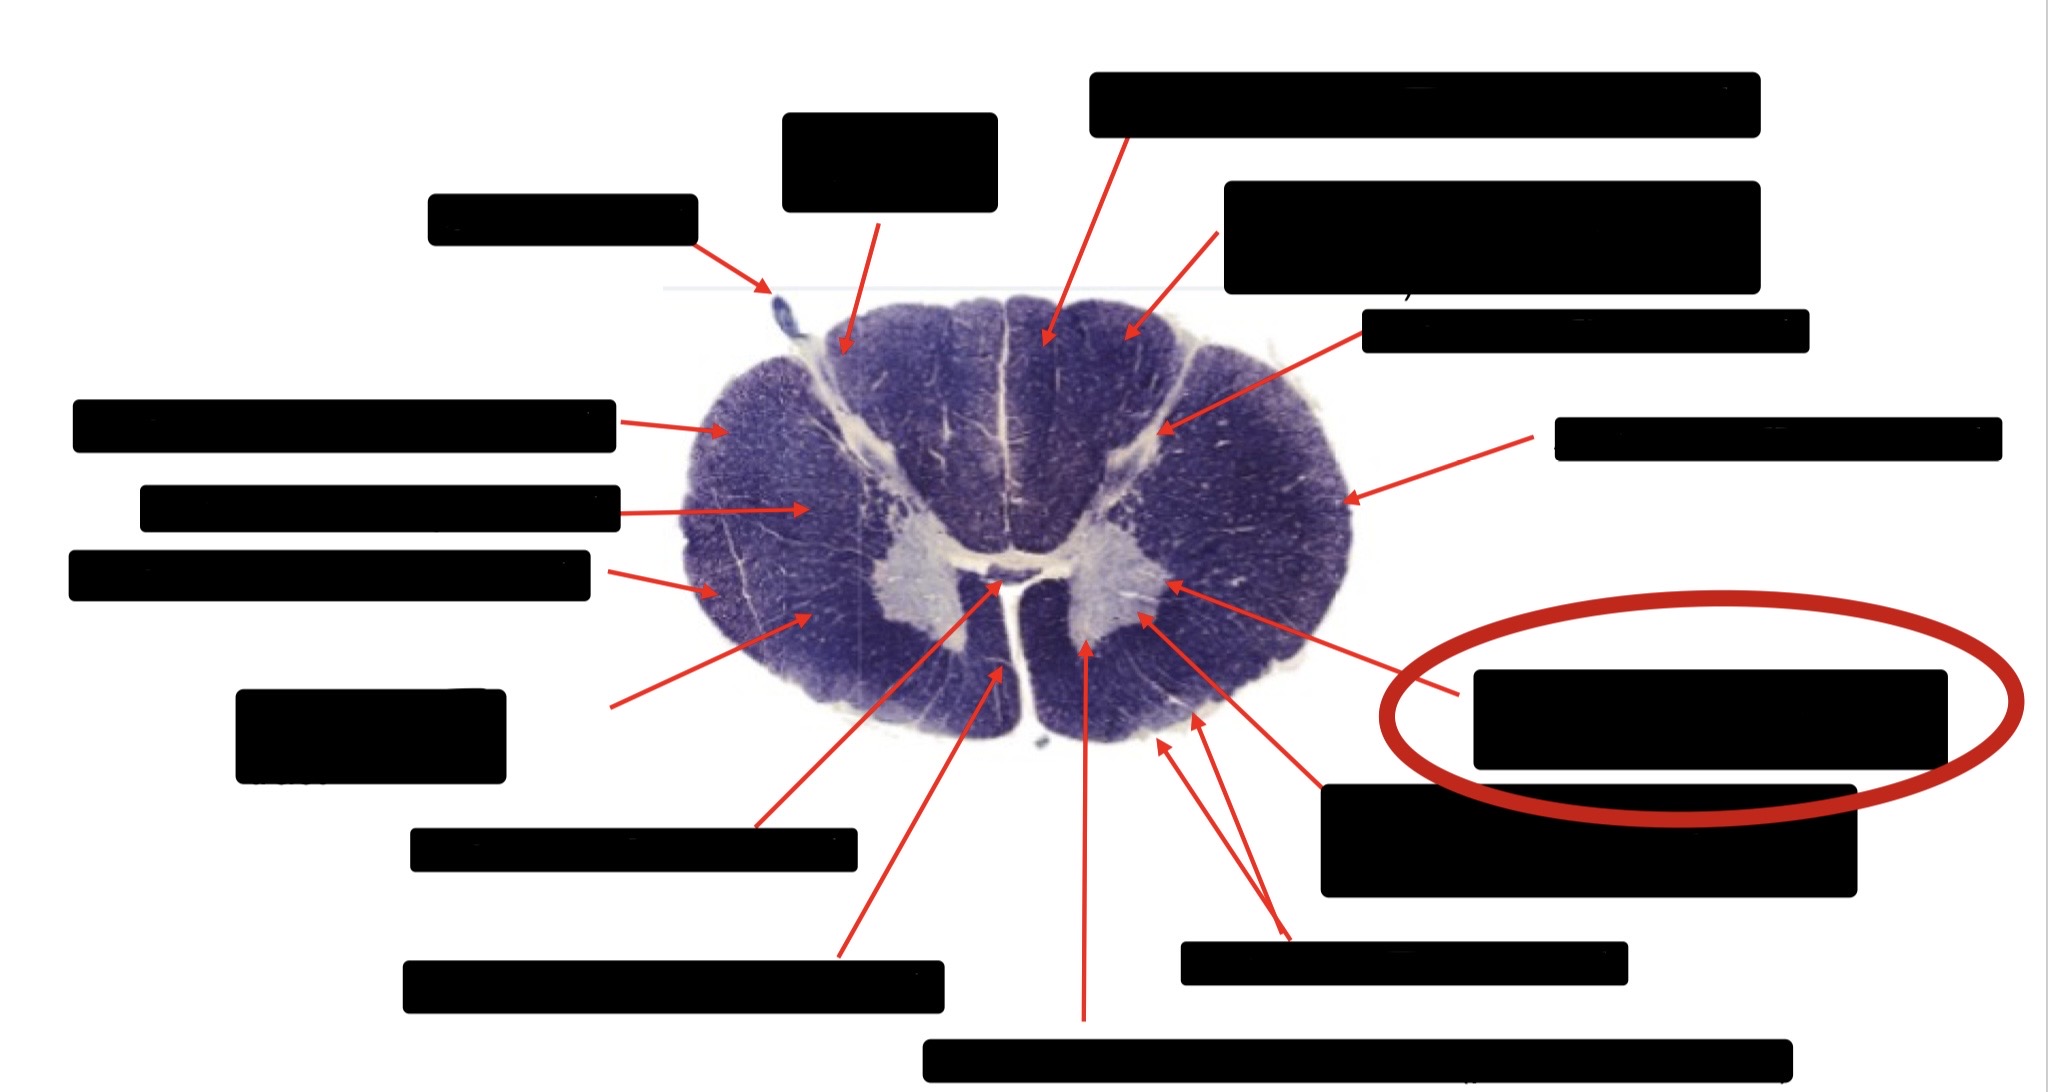

Anterior Spinal Artery

Denticulate Ligament

Ventral Root

Dorsal Root

Posterior Column Fasciculus Gracilis

Large Fiber Entry Zone

Central Canal

Dorsal Rootlet

Lissaeur’s Tract & Small Fiber Entry Zone

Substantia Gelatinosa

Lateral Corticospinal Tract

Anterior Horn Motor Neuron

Spinothalmic Tract

Anterior Horn Motor Neurons

Posterior Column

Posterior Spinocerebellar Tract

Clarke’s Nucleus

Anterior Spinocerebellar Tract

Ventral Root Fibers

Lissauer’s Tract & Small Fiber Entry Zone

Spinothalamic Tract

Anterior Horn Motor Neurons (Distal Muscles)

Anterior Horn Motor Neurons (Proximal Muscles)

Lateral Horn